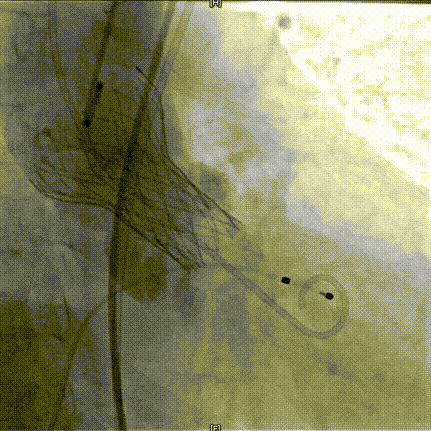

AV26瓣膜释放

完全释放后造影

TaurusElite AV26瓣膜第一次释放定位位置接近瓣环,李怡教授准确定位判断,零位释放,瓣膜在手术计划的位置牢牢站稳了!手术过程行云流水,团队配合默契,操作细致熟练,主动脉根部造影及食道超声均只有少量瓣周漏;压差由术前的100mmHg直线下降到术后的5mmHg以内,TaurusElite首秀成功!